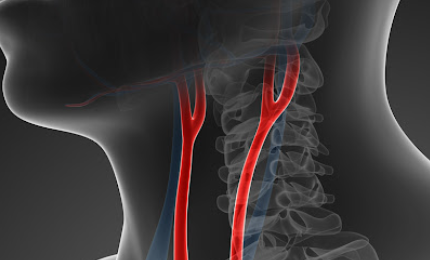

경동맥은 목의 좌우 양쪽에 있는 큰 혈관으로 심장에서 뇌로 피를 보내는 주된 혈관입니다. 뇌로 혈류를 공급하는 큰 혈관이기 때문에 이 혈관이 좁아지거나 막히게 되면 뇌졸중(중풍)의 위험도가 높아질 수 있습니다.

검사는 반드시 누운 상태에서 턱을 위로 올린 후 좌,우로 살짝씩만 돌려가며 양쪽 혈관을 관찰합니다.